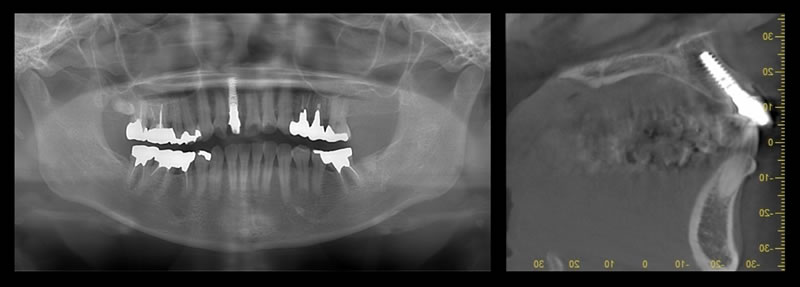

ファイナルレストレーション

仮歯を最終補綴物の取り替えて完了です。

5年経過しても美しく維持されています。